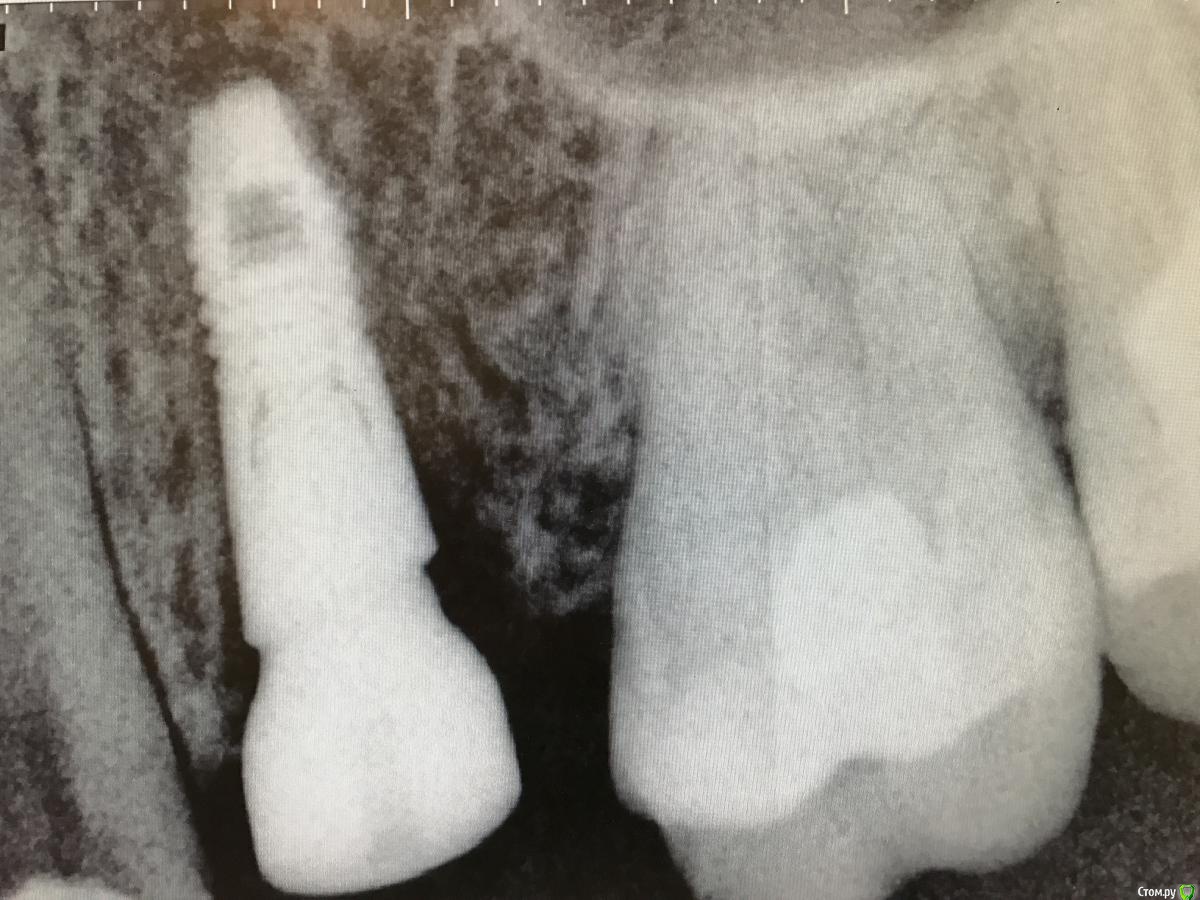

колесников Опубликовано 25 февраля, 2017 Поделиться Опубликовано 25 февраля, 2017 Здравствуйте коллеги! Представляю вашему вниманию этот клинический случай.В ноябре 2016 обратилась пациентка с жалобами на выпадение ортопедической конструкции в обл 24. Объективно: корни 24 не состоятельны. ,на десневом крае в проекции 24 свищевой ход с гнойным отделяемым.На КТ резорбция вестибулярной компактной пластинки и деструкция костной ткани в области щёчного корня.Приняв во внимание крайне негативное отношение пациентки к каким бы то ни было хирургическим вмешательствам и высоким эстетическим требованиям,было решено пойти на немедленную имплантацию .Снимки в день вмешательства,через 7,14 дней и 3мес.Имплант Astra tech profile 4.5х11мм. Сст с бугра вестибулярно. Вместо графта губки Коллапола (не вспомню причину,либо не было в наличии,либо отказ пациента). 15 Ссылка на комментарий

колесников Опубликовано 26 февраля, 2017 Автор Поделиться Опубликовано 26 февраля, 2017 Да,можно было ещё на 1мм притопить,и конечно графт вестибулярно оставить,но это стало понятно только сейчас. При постановке имплант был заглублен на 3 мм, посчитал что этого достаточно, но резорбция случилась больше планируемой. Первоначально планировалась нагрузка через 5 сут ,но ортопед позднее отказался от этой идеи. Думал заменить фдм на зебру,но пациентка пропала на 3 мес... Как получилось,так получилось. Торк был 35н/см,как обычно на астре. Ссылка на комментарий

колесников Опубликовано 12 июня, 2017 Автор Поделиться Опубликовано 12 июня, 2017 Контрольное кт спустя 3 мес. Откуда-то наросло 2мм у шейки. Ссылка на комментарий

Doctor Vlad Опубликовано 13 июня, 2017 Поделиться Опубликовано 13 июня, 2017 Откуда-то наросло 2мм у шейки. да видимо графт был, причем не коллапон коллагеновый а костная стружка, даже по первым снимкам после операции там чтото рыхлое торчит. Ссылка на комментарий